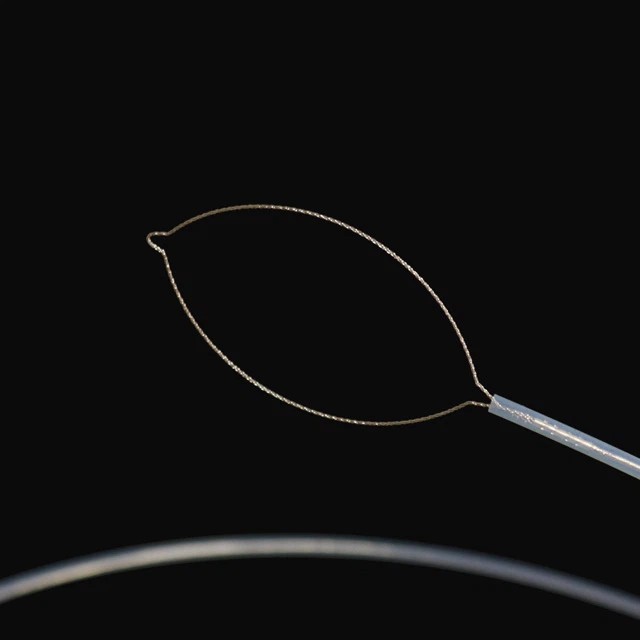

● Ici cibombelo cabikwa pamo no kubomfya kwa laiser ku kufumya no kufumyapo umubili wa cilendo mu nshila ya kugaya ifya kulya(00)}}

●Imibombele ya kubomfya bwino bwino ilalanga ubundapishi bwa pa muulu ubwapuutwamo, ukushininkisha ukubola ukwacepa ku nshila sha mu kati ishalinga ilyo balemubombacitilelandapo bwino.}

●Icibombelo cisanshamo inshila ya kupangamo ifya kupangapanga ifingi ifya kupangapanga ifyapangwa ne fintu ifya mu muulu, ukutwala ifya kupangapanga ifya pa mbali no kusunga ukulungatika ku kucingililwa kwa fintu fya ku calo cimbi ica kucingililwa ku fipe fya ku nse(2}}.